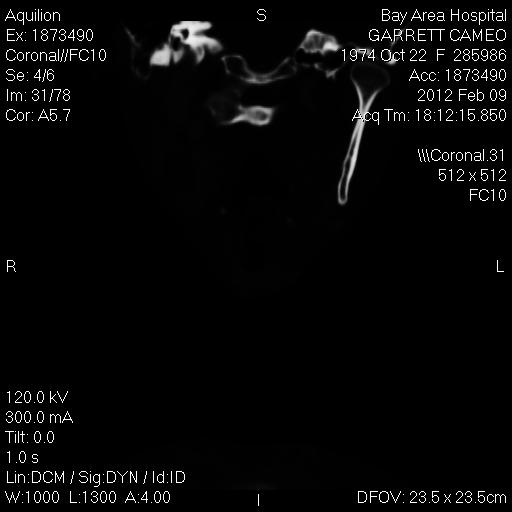

I will probably add more to CT Implant Photos #1, but I am switching right now to another view or angle. In #1 I focused on the side view of my face, neck and ear. So remember what I wrote about Princess Diana in the photos where she's laying a rectangular strip across a round landmine? You know, in Angola, where she was wearing the halo? Look at this. This is a photo that was available in 1995, because that's when the first CTs, X-rays, and MRIs were done, after the car wreck. This is a view where it's from directly above, about center of my head and then looking straight down. It cuts through right to the section where my plate is, that was placed, and underneath, the organs there include my heart. The two black round openings are the spaces for lungs. If you looked down on my head, the top of the screen there is the front of my chest and the bottom of the screen is the back of my chest. My spinal cord is in the larger hole near the bottom, and the smaller hole is where we have our throat. The slightly curved white rectangle, that is shining with rays coming forth from the metal, is the plate that is over my vertebrae. I believe there is something beneath the plate that is not just a surgical implant, but there are other photos for indications, and other places indicating implants. At any rate, if you look at the Princess Diana photos from Angola, there is one where a man is laying a curved rectangular strip across a round landmine that Di is holding, while she's wearing the halo (which is something I was told I'd have to wear bc of the wreck). How Diana knew about my photos and what was done, I'm not sure. I'm positive she knew about me. Here's the photo of the rectangular item over the landmine: http://www.google.com/imgres?start=160&num=10&hl=en&biw=1366&bih=566&tbm=isch&tbnid=ckabU5c9y0i0YM:&imgrefurl=http://www.wwenglish.com/en/voa/stan/2007/07/2007072519545.htm&docid=OQB0I5YH3dQH8M&imgurl=http://www.wwenglish.com/up06/2007/07/19545/4.jpg&w=210&h=176&ei=z58XUKuwL5SM6QGN74GYBw&zoom=1&iact=hc&vpx=928&vpy=312&dur=787&hovh=140&hovw=168&tx=111&ty=104&sig=104145628167857980544&page=10&tbnh=140&tbnw=168&ndsp=17&ved=1t:429,r:4,s:160,i:247. She was with, I believe, a man by the name of Carlos Silva. That was in 1997. In 1997 I was friends with a man from Nicaragua named Carlos Sequiera and he married a woman named Lisa who moved from Alaska to Portland. They had a very active interest in me at the time. I think I'm going to put up one set and then flip it.